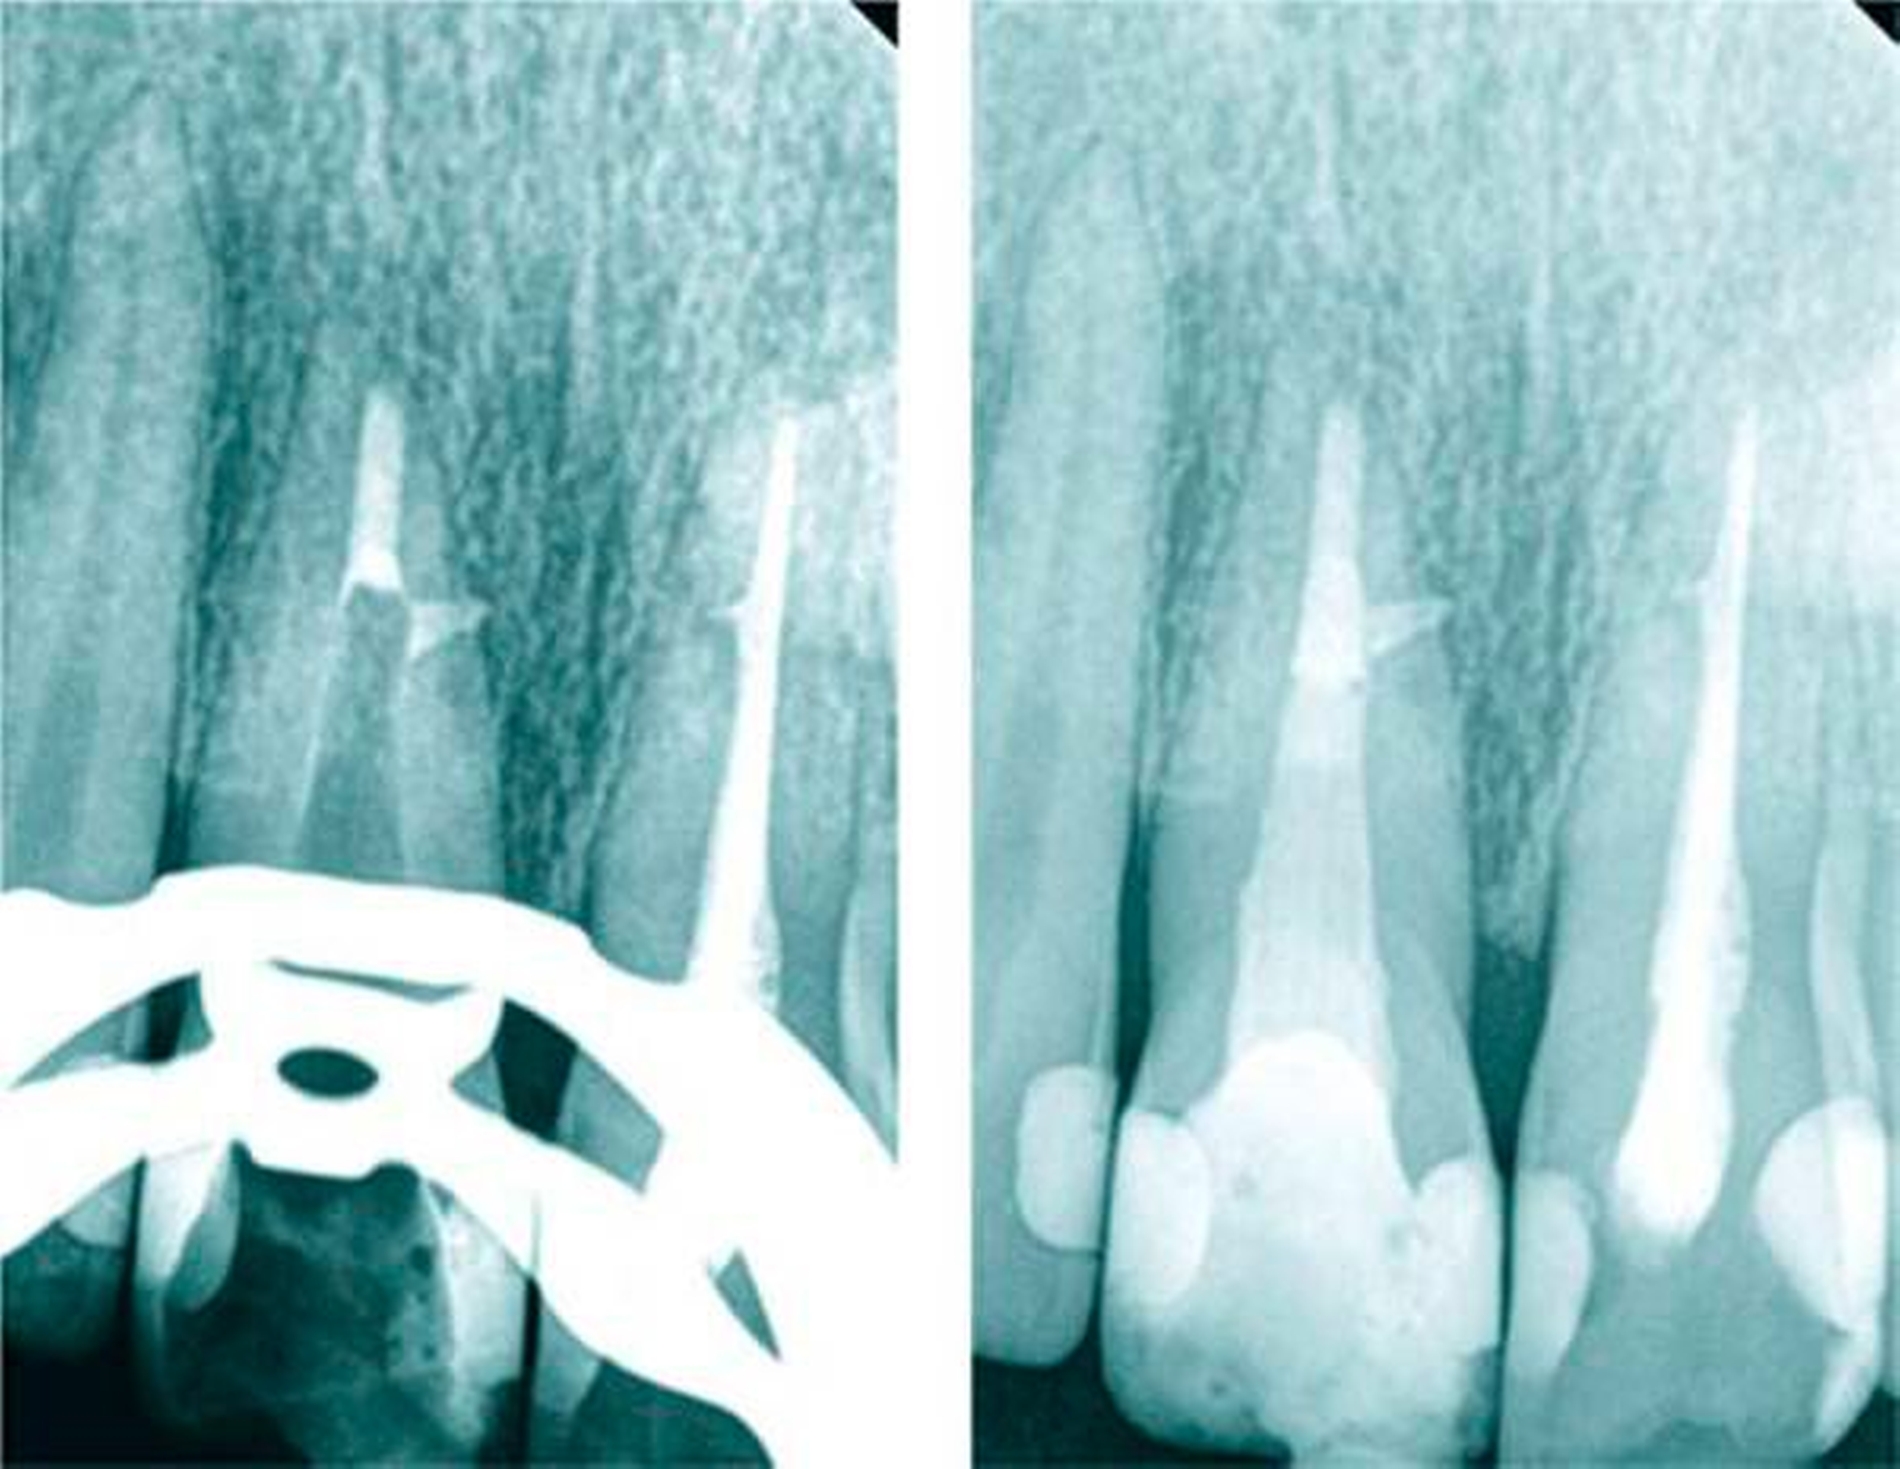

Kariesfolgeerkrankungen und traumatische Verletzungen sind die häufigsten Ursachen für eine endodontische Therapie. Insbesondere traumatische Verletzungen im Kopfbereich führen oft zu Verletzungen der Frontzähne mit pathologischen Veränderungen der Pulpa. Konkussions- und Dislokationsverletzungen können bei Erhalt der Pulpa und fehlender mikrobieller Infektion zu einer raschen Produktion von irregulärem Tertiärdentin (Osteoid) führen [Six et al., 2001; Mjör, 2002; Ørstavik & Pitt-Ford, 2008]. Degenerative und reparative Reaktionen der Pulpazellen können auch als Folge von Karies zur Bildung von Tertiärdentin, Dentikeln und verstärkter Mineralisation oder Fibrosierung der Pulpa beitragen. Dies kann sowohl das Auffinden des Wurzelkanaleingangs als auch das Erschließen und Erweitern des Wurzelkanals erheblich erschweren (Abbildung 1).

25 Prozent aller Wurzelkanalbehandlungen finden an Frontzähnen statt. Im Vergleich zu Molaren und Prämolaren werden an Frontzähnen danach häufiger Revisionen, Wurzelspitzenresektionen und Extraktionen nötig [Rädel et al., 2014]. Trotz scheinbar einfacher Anatomie treten im Verlauf von Wurzelkanalbehandlungen Komplikationen auf, die wiederholte endodontische oder endo-chirurgische Therapien nach sich ziehen können – mit unsicherer Prognose (Abbildung 2). Eine möglicherweise verkannte Ursache ist die nicht immer leicht zu erkennende variable Anatomie des Wurzelkanalsystems und die im Verlauf der Alterung von Pulpa und Dentin sich vollziehenden Veränderungen dentaler Gewebe [Ørstavik & Pitt-Ford, 2008].